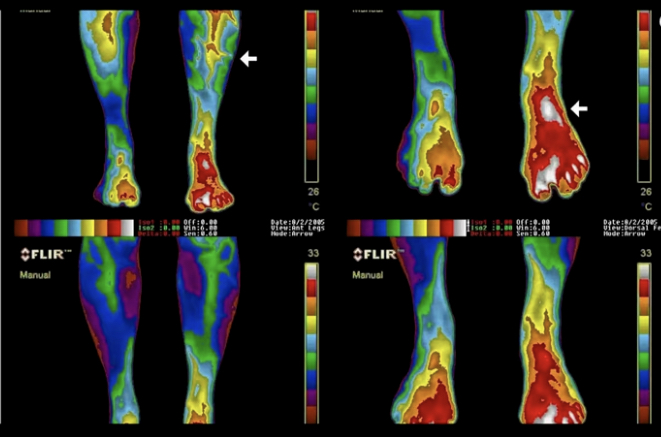

☀️ Împământarea este deci echivalentul mersului desculţ pe pământ, prin iarba. Este o metodă de energizare a corpului care este la îndemâna oricui şi nu costă nici nimic. Reprezintă conectarea corpului la câmpul energetic al Pământului, corpul nostru fiind şi el format din energie, minerale şi apă, asta traducându-se prin faptul că este un conducător de electroni. Aceşti electroni pe care îi contine Pământul, atunci când umblăm desculţi, ajung în corpul nostru. Fiind aprope tot timpul expuşi la radiaţii, corpul nostru dezvoltă electroni pozitivi care formează radicalii liberi. Când intrăm în contact direct cu Pământul, acesta acţionează ca o sarcină negativă, anulând electronii pozitivi.

☀️ Experţii spun că împământarea modifică activitatea la nivelul creierului, ajută corpul să se vindece mai uşor şi mai rapid, reduce stresul, scade nivelul de glucoză din sânge, creşte imunitatea, îmbunătăţeşte digestia şi calitatea somnului.

☀️ Totodată s-a demonstrat că mersul în picioarele goale prin iarbă îi poate ajuta pe cei care suferă de boli cronice, reducându-le durerile.